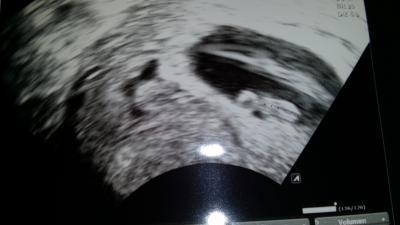

Hallo liebe Mamis, ich war ja am Montag wieder beim Frauenarzt. Das Herzchen bummert laut und stark.... und ist auch sehr regelmäßig :-D Die Blutungen haben leider nicht aufgehört.Ich dachte schon weil ich seid fast einer woche kein blut mehr gefunden habe aber beim Ultraschall (schwarze linien rechts im Bild) sah man die einblutungen noch :-( ich hoffe das lässt endlich bald nach.Würmchen gehts soweit aber ganz gut.... und das ist ja das wichtigste... jetzt nur morgen sehen wie das mit der Arbeit weiter geht :-/ Immer das gleiche Thema... Ps: Das runde rechts im Bild ist nicht der Kopf sondern der Dottersack ^^ hahahahahaha

Sorry...muss meinen eigenen Beitrag beantwirten...der hat mein Bild umgedreht also ist jetzt alles was ich rechts meinte....links ^^ hahahaha

Schön, dass es deinem Krümel gut geht!!! Bei mir sah man im Ultraschall vor einer Woche ähnliche schwarze Stellen, obwohl ich (bis jetzt, 6+6) keine Blutungen habe. Meine Ärztin meinte nur, dass das eine Schwachstelle sei und man nur abwarten könne. Das verunsichert, der nächste Termin ist erst am 27. August... Darf ich fragen, was dein Arzt sagt? LG Tanja

Danke Mädels :-) @Tan81: Also mein Arzt sagt das so eine Blutung erstmal oft in der Frühschwangerschaft auftritt und nicht wenig.Wenn die Plazent sich aufbaut dann mit Ihr auch 1000 und mehr neue Adern.Manche größer und stabiler...manche kleiner.Wenn du niest...dich ruckartig bewegst oder einfach so.... platzen diese Adern manchmal und bilden einen Bluterguss.Das Blut fließt nicht immer ab.Ich habe seid über einer Woche keine Blutungen mehr gesehen und trotzdem sind Sie da.Solange das alles nicht dirket an der Fruchtblase sitzt oder eher am Mutterkuchen.... ist das alles halb so wild.Was meint deine Ärztin/Arzt damit? Der Satz ist dkch ziemlich verwirrend... lass dich nicht verrückt machen! Deinem Würmchen wird es gut gehen...